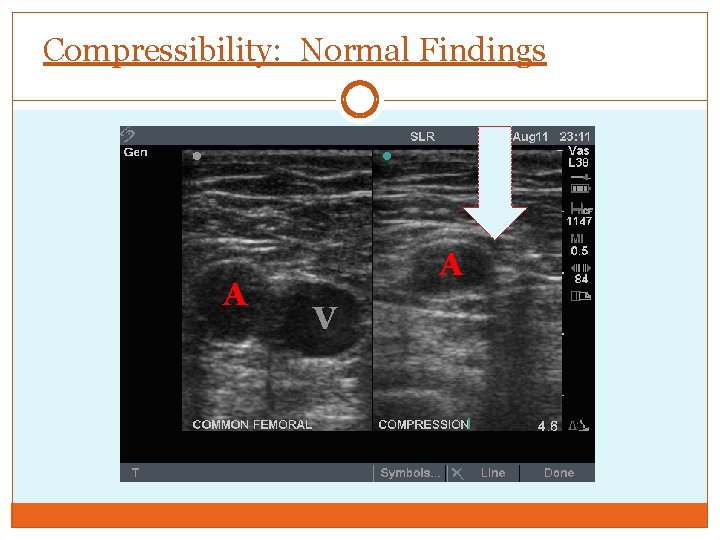

Major Criteria: Compressibility Collapse of lumen of vein - Complete apposition of anterior and posterior wall Compress with transducer in transverse - Longitudinal compression slides off vessel wall leading to false negative - Use to follow course of vein May visualize thrombus; not necessary for diagnosis

Compressibility: Normal Findings A A V